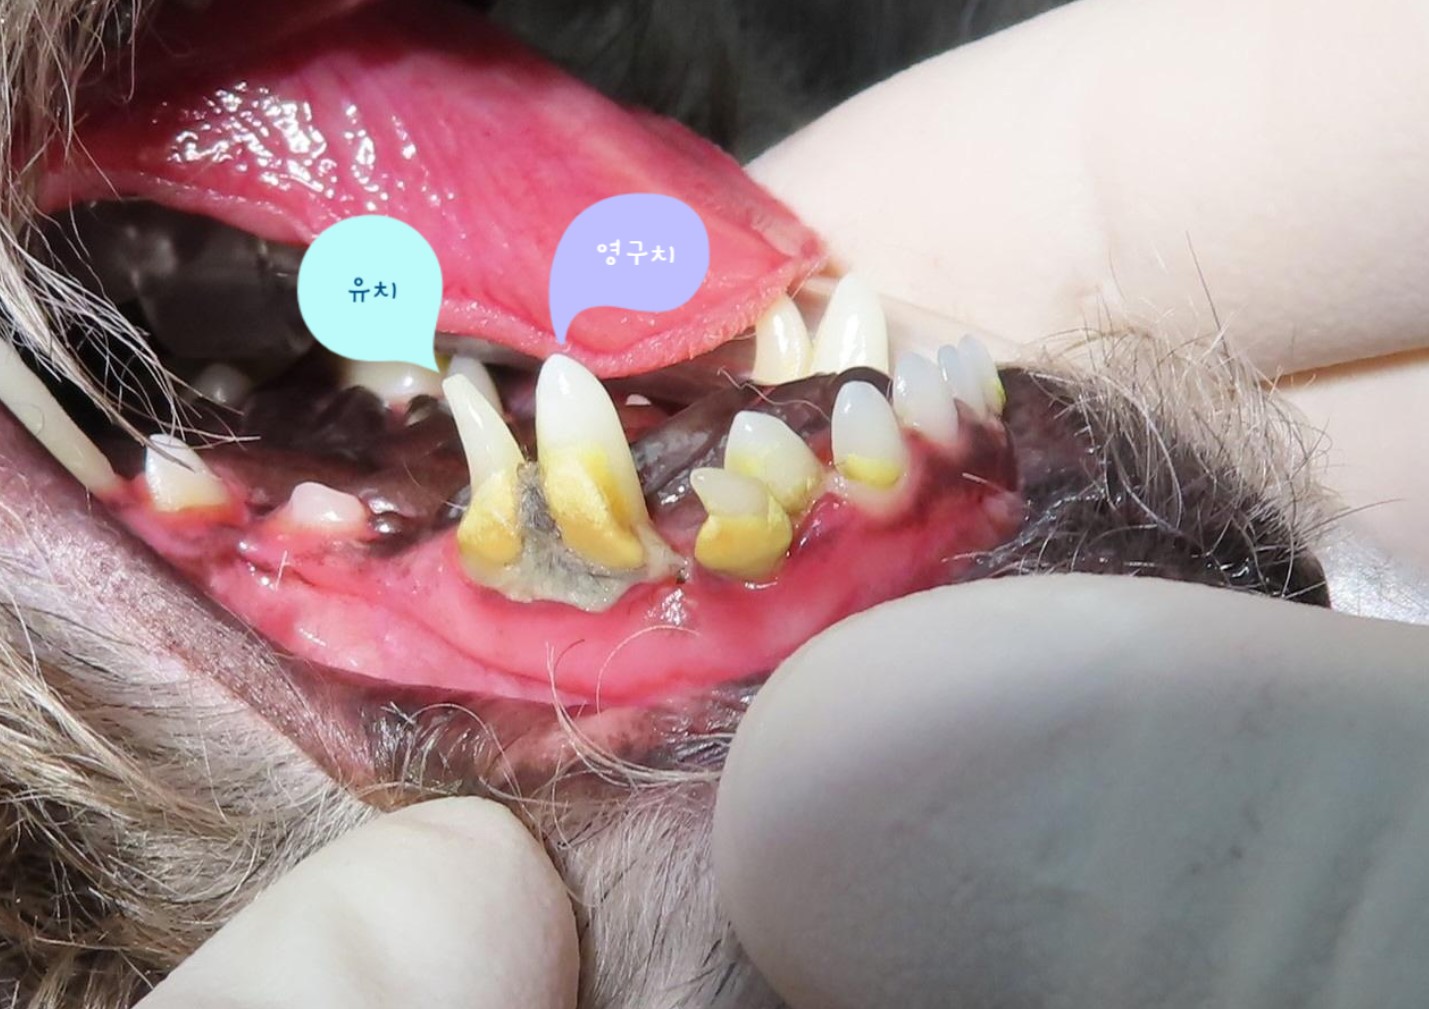

다음은 본원에 내원하여 잔존 유치를 발치한 사례입니다.

이번 사례는 송곳니 유치가 제때 빠지지 않았을 때 생길 수 있는 문제와 그 해결방법에 대하여 말씀드리고자 합니다.

강아지 치아를 관찰해 보면 덧니가 쌍으로 있는 경우가 있습니다.

흔히 덧니라고 알고 있는 치아가 탈락되지 않은 잔존 유치인 경우가 많습니다.

잔존 유치가 탈락되지 않아 영구치가 치아 사이에 같혀 있음 위 사진은 유치가 제때 탈락되지 않아 영구치가 세 번째 앞니 아래에 갇혀 있는 것을 보여줍니다.

세 번째 앞니도 송곳니 간섭으로 인해 정상위치 보다 위쪽으로 벗어나 있는 것(deviation)을 확인할 수 있습니다.